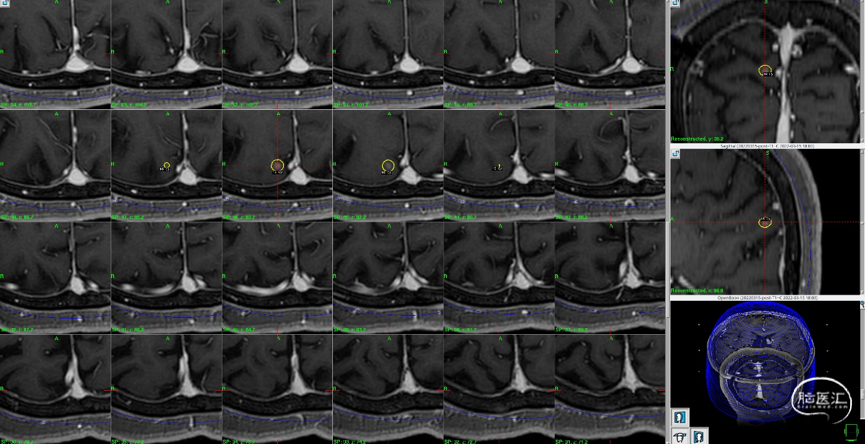

磁共振MRI定位扫描(T2平扫,2mm轴位连续断层+T1增强序列,1mm轴位连续断层薄扫)。

制定立体定向伽玛刀治疗计划(术中薄扫核磁扫面共发现4个病灶,除术前的2个病灶外,还发现2个小病灶);

2)右侧侧脑室壁病灶体积缩小显著:

影像随访:

1)左额病灶:囊性病变逐渐缩小

6个月随访时,薄扫增强磁共振(1mm/层)提示肿瘤明显缩小,无放射相关不良反应,没有新发病灶;患者目前仍在规律的随访当中,期待我们的长期随访结果。